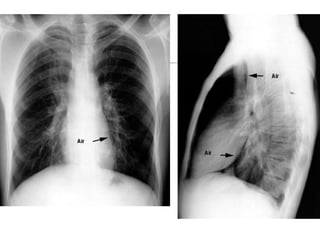

Radiographic Signs of Pneumomediastinum

Subcutaneous emphysema

Thymic sail sign

Pneumoprecardium

Ring around the artery sign

Tubular artery sign

Double bronchial wall sign

Continuous diaphragm sign

Extrapleural sign

Air in the pulmonary ligament

• 82.

Radiographic Signs ofPneumomediastinum Subcutaneous emphysema Thymic sail sign Pneumoprecardium Ring around the artery sign Tubular artery sign Double bronchial wall sign Continuous diaphragm sign Extrapleural sign Air in the pulmonary ligament